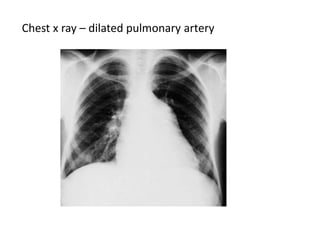

Chest x ray – dilated pulmonary artery

Chest x ray– dilated pulmonary artery